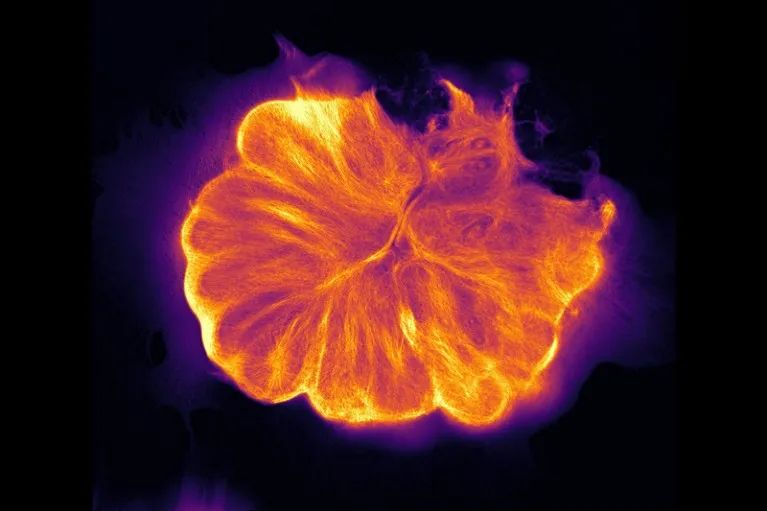

移植到小鼠大脑两个月后的人类脑细胞及其细胞核。来源:Raquel Real, Manuel Peter, Rick Livesey and Vincenzo De Paola

与Vanderhaeghen所做的移植不同,De Paola的移植在小鼠大脑中最终生长成了密集的人体组织微移植物,而且一直存活到5个月后实验结束。“我们对生长量感到惊讶,它形成了一个庞大网络,”De Paola说,“当然了,‘庞大’是相对而言,实际上大概和一个大的滨豆差不多。”

De Paola表示,被移植的细胞所产生的连接大部分都是发生在被移植细胞之间的(超过90% 的连接是被移植的人类细胞相互之间的),但这些人类细胞也确实向小鼠大脑皮层的其他部分发出神经投射,并从小鼠大脑中接受了一些神经投射、血管和免疫细胞。这些支持使这块组织能够持续发育达5个月,并能做出那些预期出现于发育中人类胎儿大脑的行为,即修剪神经元细胞分支和细胞间连接,并开始以协同方式放电。